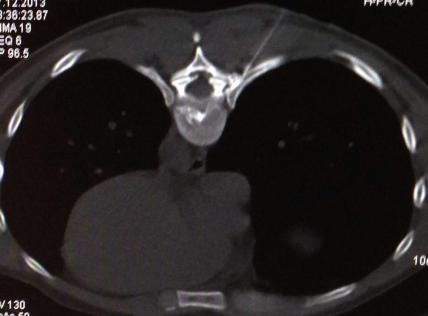

With the help of an X-ray the surgeon inserts a thin needle into the intervertebral disk. Due to the administration of analgetics the entire intervention is nearly pain free. By the help of the needle the surgeon can then insert a glass fiber which carries a laser. The slipped disk can then be vaporized by a laser.